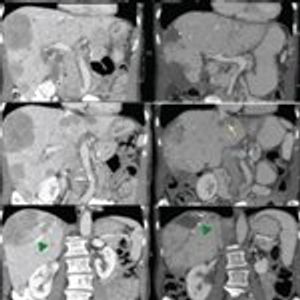

In this review, we focus on the treatment of well-differentiated early and metastatic PNETs, emphasizing current controversies, recent advances in therapy, and the multidisciplinary approach required for optimal treatment.